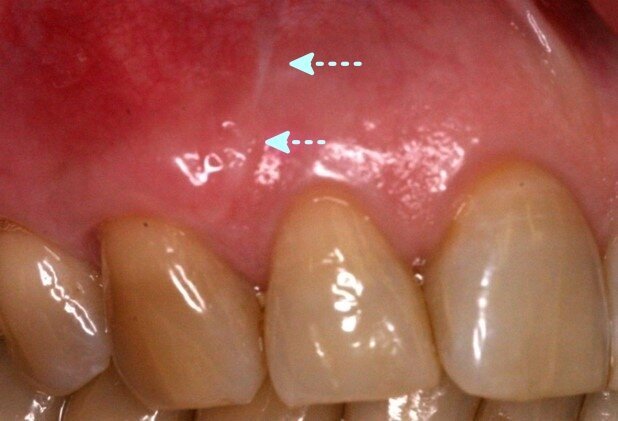

Fig. 6: Vertical release incisions in esthetic zone can often lead to scar tissue visible even 7 years post-op

We recently compared the long-term (7 years) results in the anterior esthetic zone between 2 groups of patients- with and without vertical release incisions (Bhatavadekar et al., 2020). At both the 8 months and 7-year follow-ups, the group without vertical release demonstrated statistically superior root coverage and keratinized tissue zone.

Importantly, it was observed that in the anterior esthetic zone, vertical release incisions left scar tissue which was often visible even at the 7-year mark (Fig. 6). This was in spite of the fact that the vertical incisions were always made at line angles, avoiding areas of root prominence.

Vertical release incisions in esthetic areas can leave scar tissue visible up to 7 years post-op, as per the results from our publications. Hence, judicious use of vertical release incisions is mandated in high visibility esthetic zones.